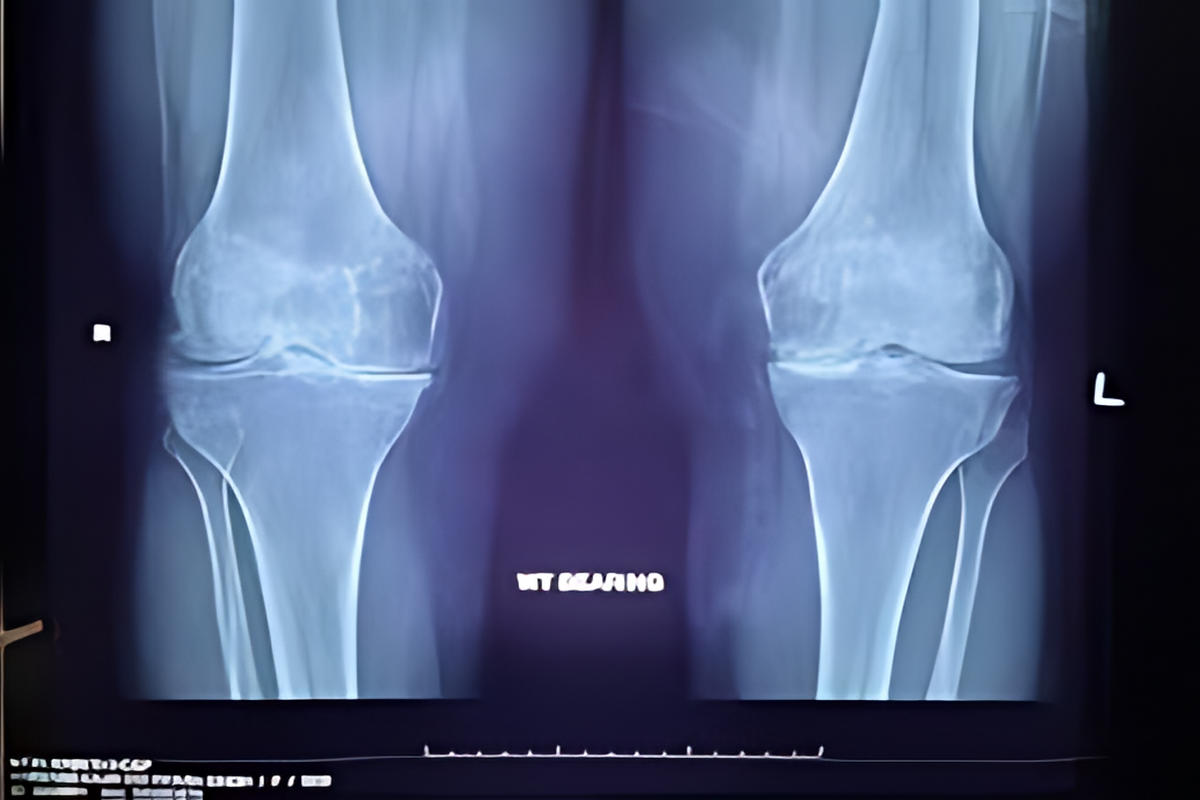

Η αρθρίτιδα είναι μία εκφυλιστική και συχνά φλεγμονώδης πάθηση της άρθρωσης, κατά την οποία καταστρέφεται σταδιακά ο αρθρικός χόνδρος. Η απώλεια του χόνδρου οδηγεί σε άμεση τριβή των οστών μεταξύ τους, προκαλώντας πόνο, δυσκαμψία και, σε προχωρημένα στάδια, παραμόρφωση της άρθρωσης.

Το πιο συχνό σύμπτωμα είναι ο πόνος στο γόνατο, ιδιαίτερα κατά την κίνηση ή τη φόρτιση. Πολλοί ασθενείς αναφέρουν δυσκαμψία μετά από ξεκούραση ή τις πρωινές ώρες, καθώς και οίδημα της άρθρωσης.

Κατά την κίνηση μπορεί να ακούγεται ή να γίνεται αισθητό «τρίξιμο», ενώ στα προχωρημένα στάδια εμφανίζεται παραμόρφωση του γόνατος και σημαντικός περιορισμός της κινητικότητας.